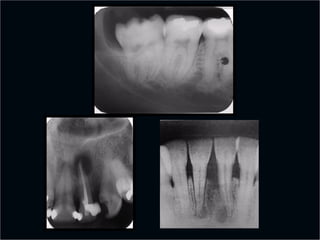

Lesiones

Periapicales

Desde el punto de vista rx

 Línea periodontal apical engrosada

 Granuloma

 Quiste

 Osteítis

 Osteítis condensante

Linea Periodontal

Apical Engrosada

Línea Periodontal

Causas

 Periodontitis apical

crónica

 Trauma oclusal

 Distorsión por

amplitud

 Sumación de

absorciones

Granuloma

 Area radiolúcida

 Redonda u oval

 Límites netos

 Generalmente no

corticalizado

 Tamaño variable (no

mayor a 1 cm)

 Signos de infección

pulpar